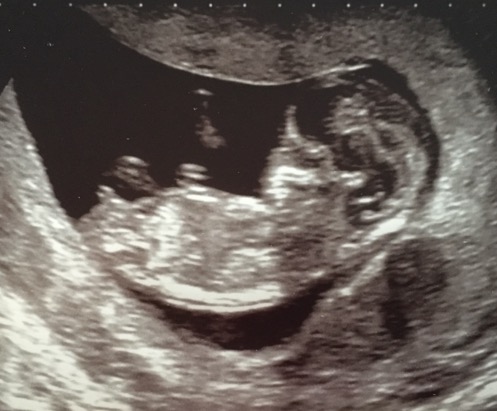

I'm back after 100% correct guesses on my first baby in 2013, not sure these pics are that good but I've got an idea which colour I think, just wondering if others think the same. These pics are from 11+6. Thank you :)